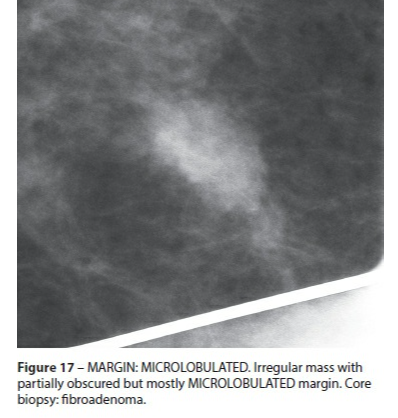

Microlobulée

- Suspect